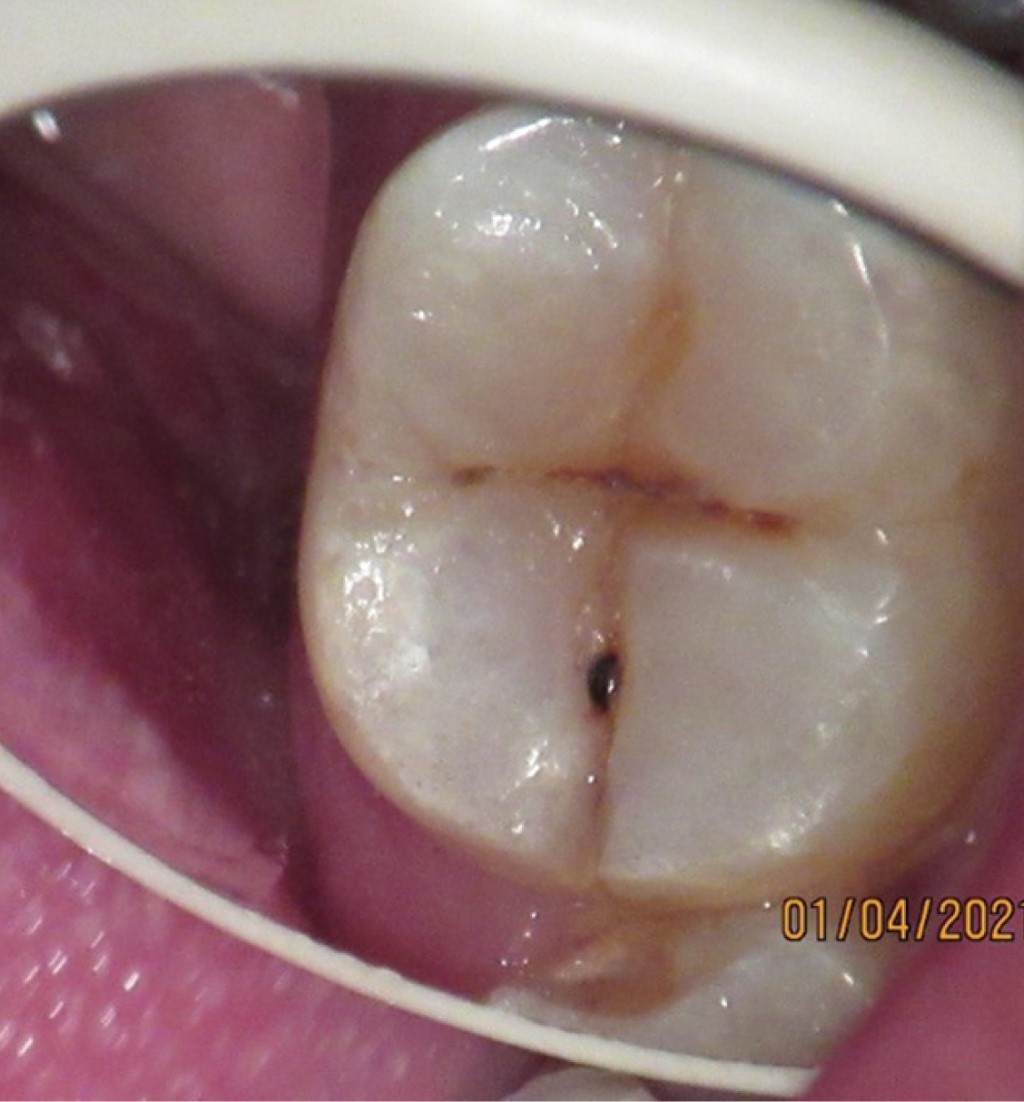

Figure 1

Figure 2

Figure 3

Figure 4